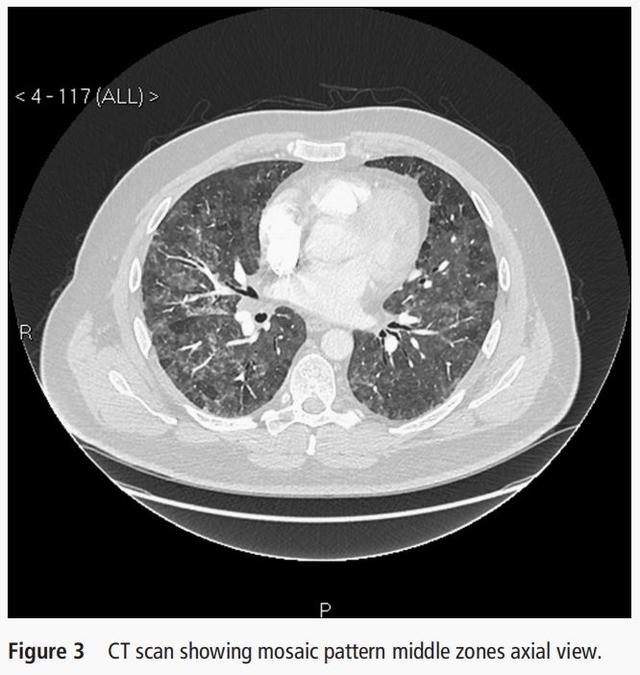

- 胸部CT显示双肺弥漫分布的马赛克 , 也不支持结节病 。

- 胸部CT显示双肺弥漫分布的马赛克 , 呼吸困难逐渐加重 , 肺功能示限制性通气功能障碍 , 弥散功能下降 , 目前考虑过敏性肺炎可能性最大 。